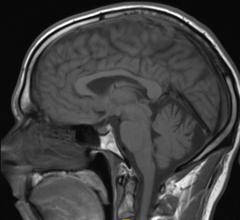

A new study by the Harvey L. Neiman Health Policy Institute found that in the Medicare population, the utilization rates have increased in both volume and per beneficiary over the past two decades for the most common musculoskeletal (MSK) extremity imaging modalities. The study focused on radiography, magnetic resonance imaging (MRI), computed tomography (CT) and ultrasound.

MRI Distortion Check is a new, cloud-based solution designed to quickly and automatically quantify distortion in magnetic resonance images (MRI). Used in conjunction with CIRS MRI Grid phantoms, the software provides the capability to quickly and accurately measure distortion through out the entire image volume.